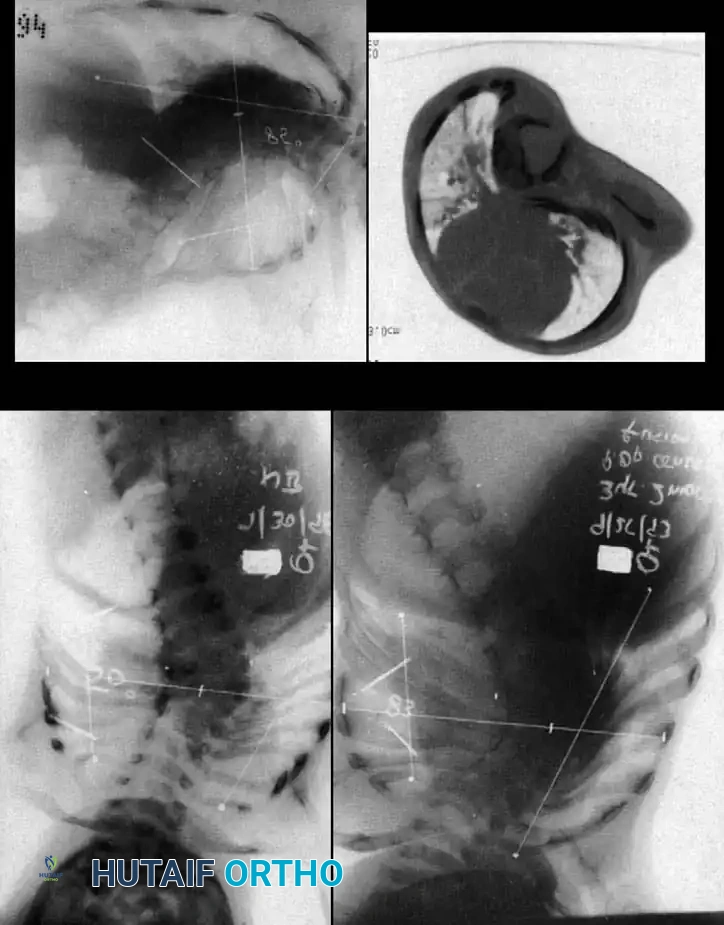

Image

Surgical planning and execution of complex congenital curve corrections.